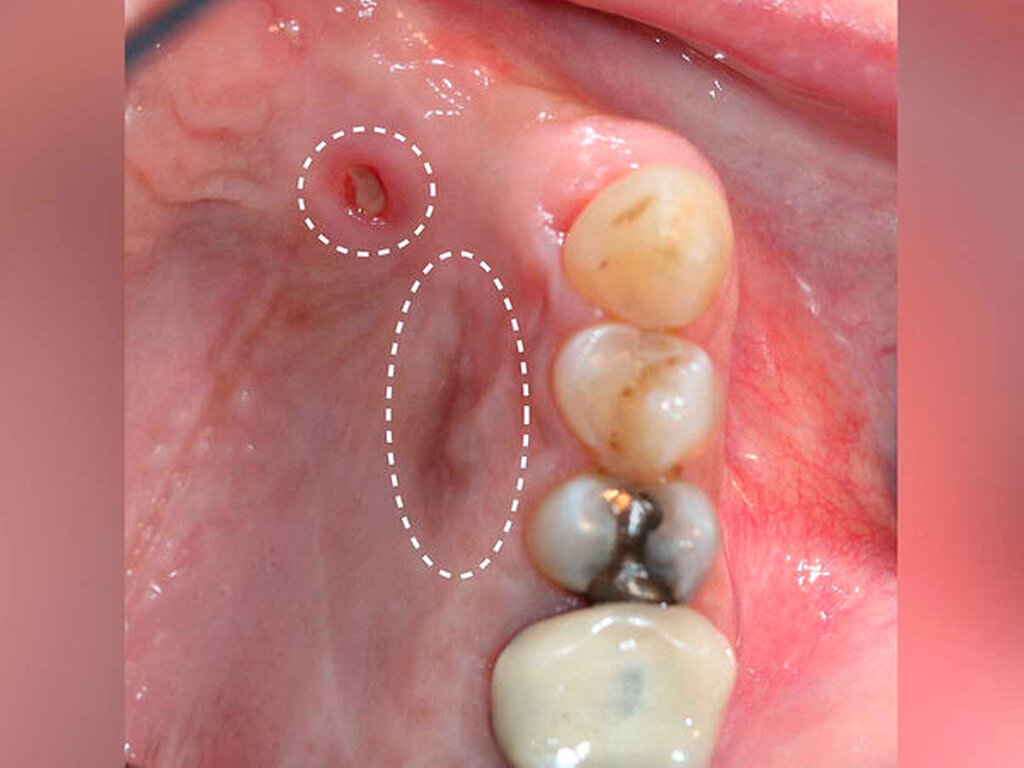

Bei der Aufnahmeuntersuchung zeigte sich eine schwärzliche, circa 2 cm x 1,5 cm messende, unregelmäßige Makula der Mundschleimhaut mit unscharfer Begrenzung, die sich von der marginalen Gingiva in regio 11 in Richtung des harten Gaumens erstreckte (Abbildung 1). Die sonografische Untersuchung der Halsweichteile war unauffällig, die Panoramaschichtaufnahme zeigte einen konservierend und prothetisch suffizient versorgten, altersentsprechenden Normalbefund. Die Schleimhautveränderung war bereits klinisch hochgradig verdächtig auf ein Mundschleimhautmelanom.

Nach drei Monaten war erneut eine circa 2 mm x 2 mm große schwärzliche Mundschleimhautveränderung in regio 012 auffällig (Abbildung 4). Die Raumforderung inklusive einer kortikalen Knochenspange des Alveolarkamms und des Os palatinum von regio 13 bis regio 23 wurde großflächig reseziert. Histopathologisch wurde ein R0-reseziertes Rezidiv des vorbekannten Melanoma in situ bestätigt, eine tiefere Tumorinfiltration über die Basalmembran hinweg oder sogar bis in den ortsständigen Knochen konnte ausgeschlossen werden.